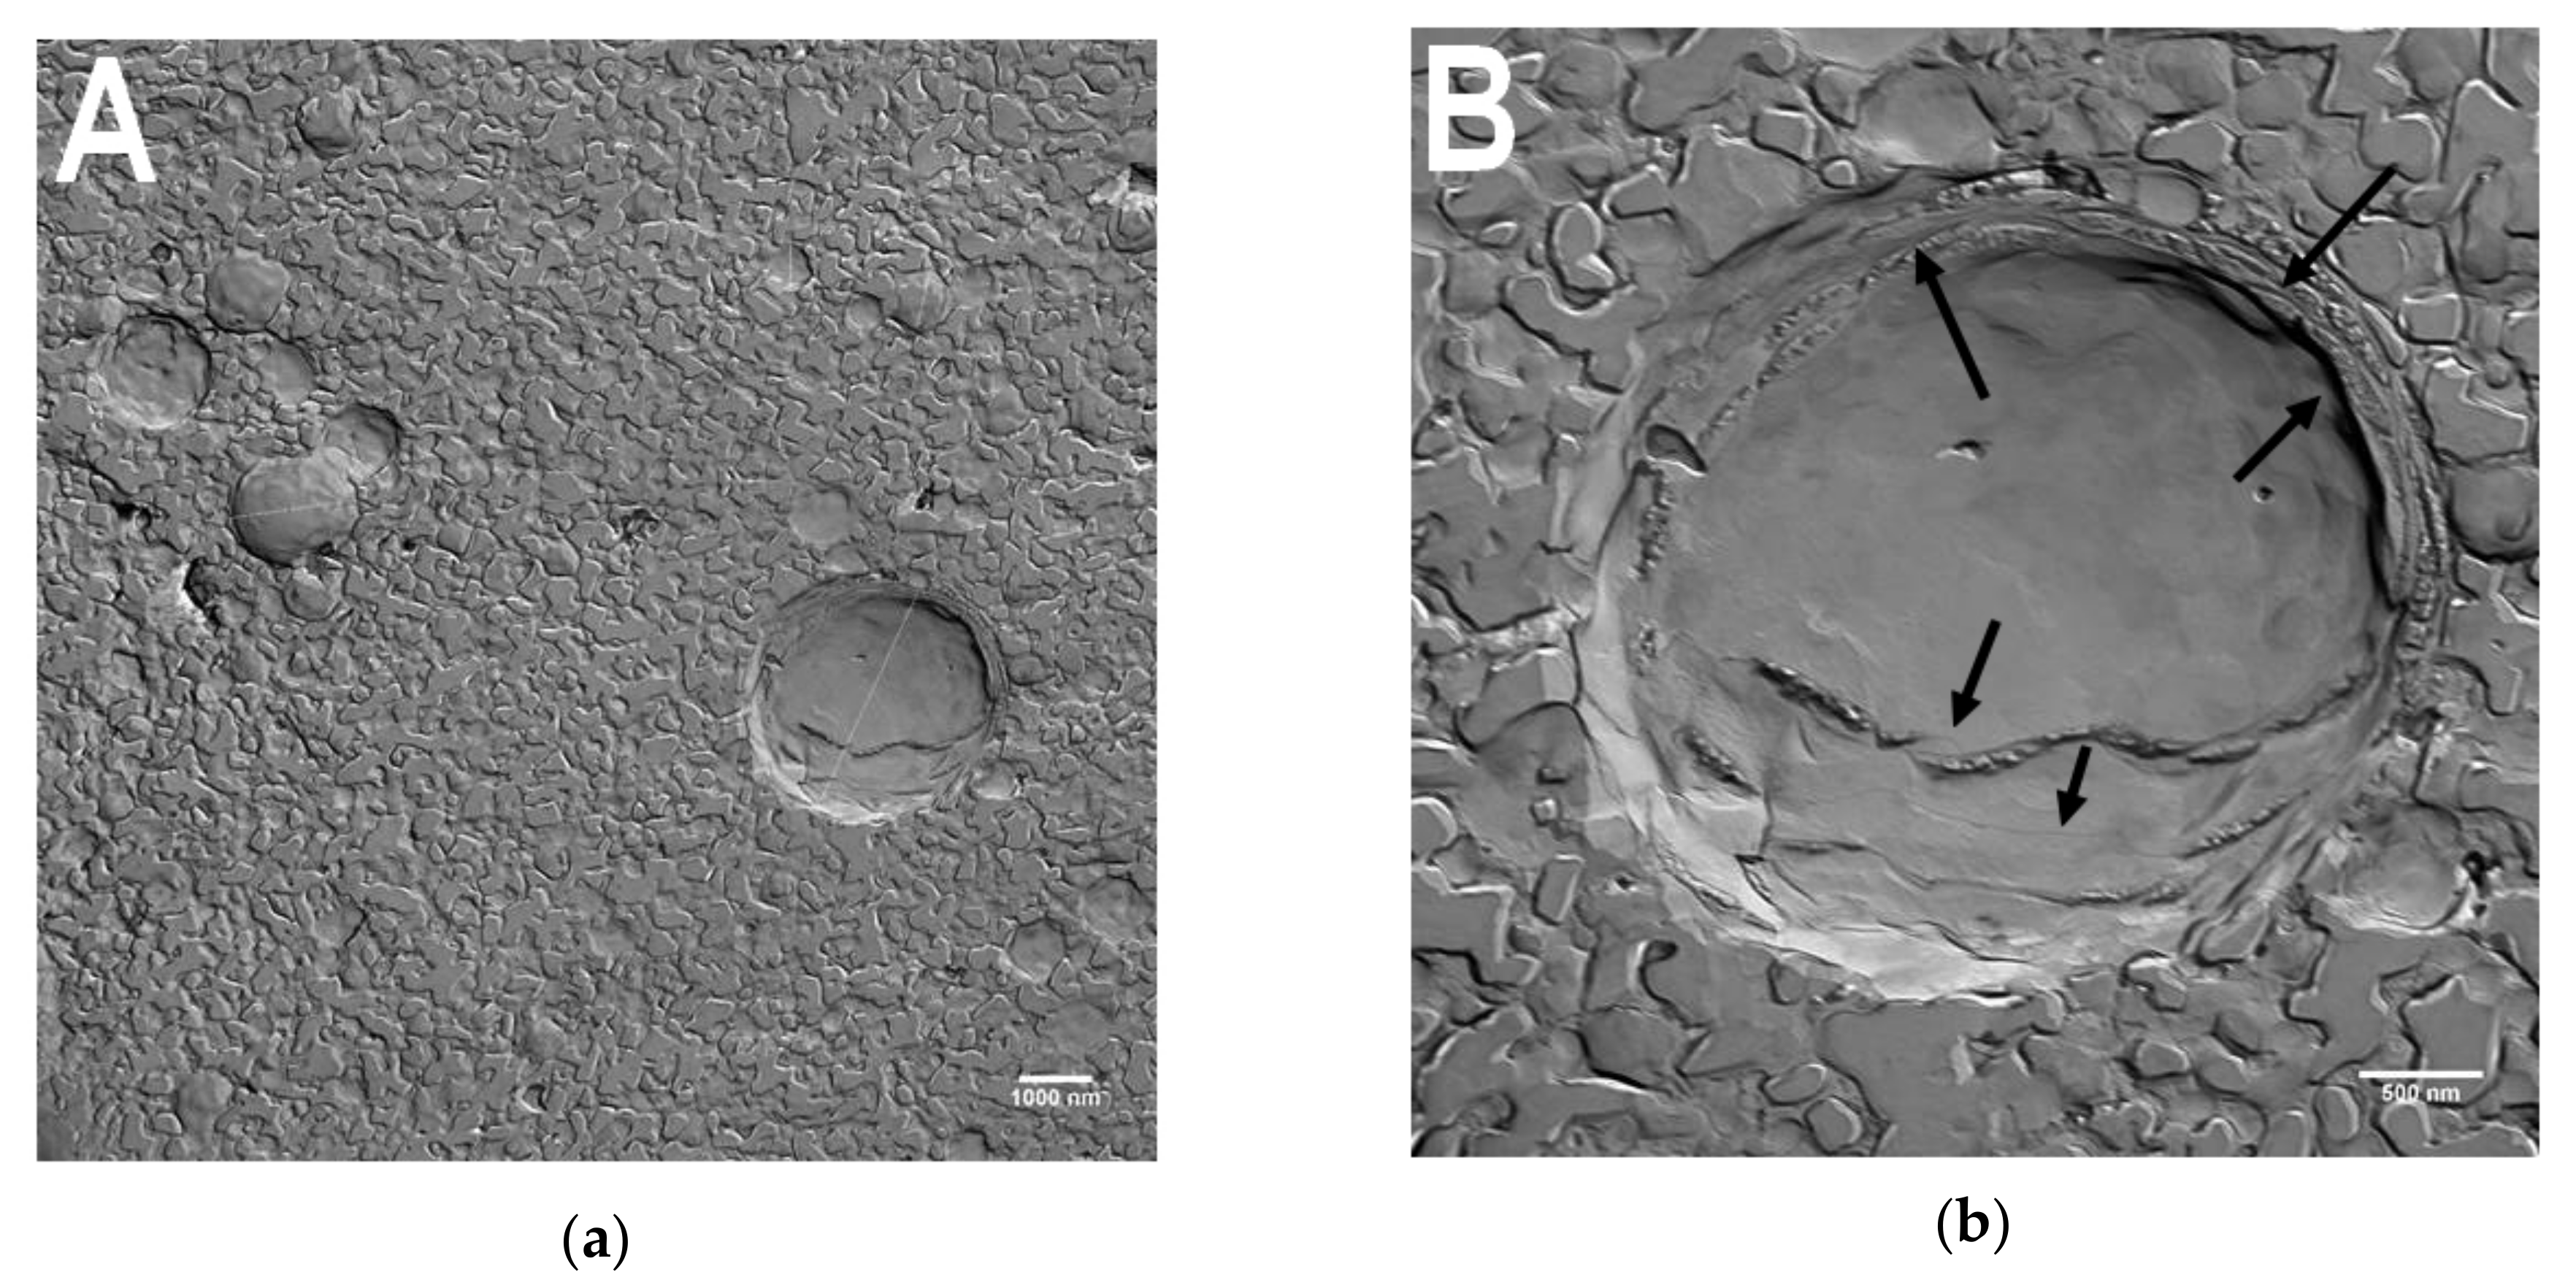

3.2. Freeze-Etching